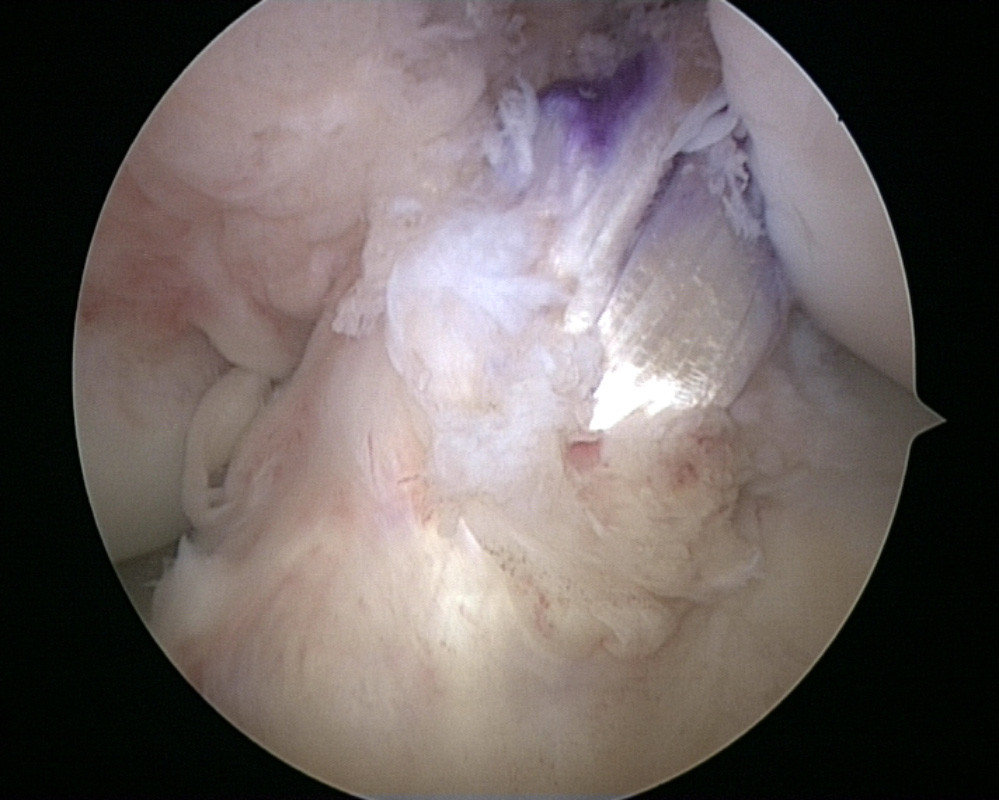

Kreuzbanderhalt bei Teilrupturen durch Healing Response Technik

In Fällen in denen das vordere Kreuzband nur zum Teil direkt am Knochen abgerissen ist können durch eine Anmeiselung des freiliegenden Knochens Stammzellen freigesetzt und eine stabile Vernarbung erreicht werden. Diese Technik wird als „Healing Response“ bezeichnet.